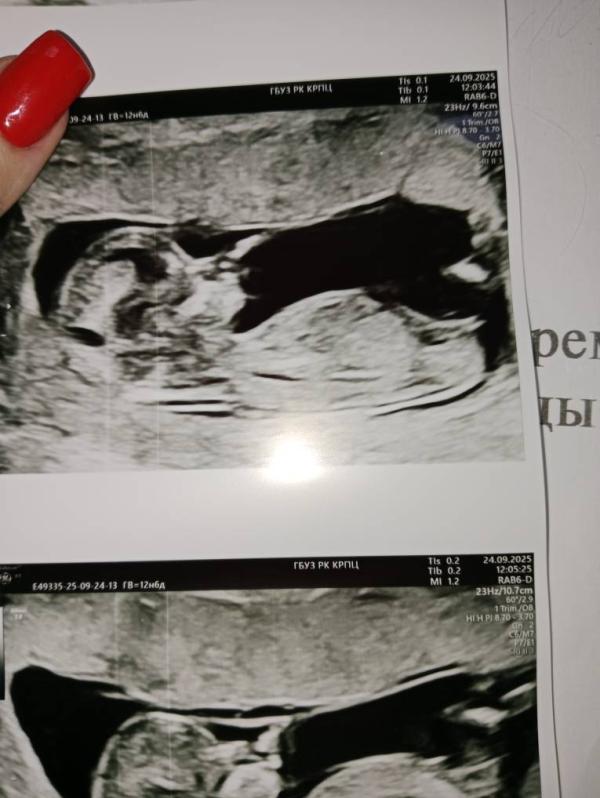

Первый скрининг в 12.6 недель: все хорошо, предположили девочку

Срок 12.6.

Первый скрининг пройден,все хорошо 🙏

Предположили 70% девочку

Половой бугорок у вас девчачий, поздравляю 😍